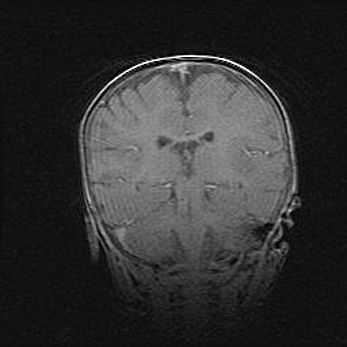

Неполная лизэнцефалия (пахигирия). Открытая гидроцефалия.

Возраст: 17 дней

Вес: 3110 г

Пол: мужской

Окружность головы: 33,5 см

Срок гестации: 35-36 недель

Лизэнцефалия—недоразвитие корковой пластинки и мозговых извилин в результате нарушения миграции нейронов коры. Поверхность мозговых полушарий гладкая. Микроскопически выявляется отсутствие нормальных слоев коры и скопление групп нейронов в подкорковом белом веществе.

Пахигирия—уменьшение числа вторичных извилин. В пораженном полушарии нервные клетки образуют толстый недифференцированный слой с неправильно расположенными нервными волокнами и группами гетеротопных клеток. Нервные клетки незрелые. Белое вещество истончено. При этом нередко аномально развит корково-спинномозговой путь.